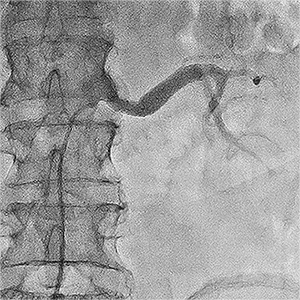

Приклади ангіограм:

стеноз правої ниркової артерії    пухлина підшлункової залози

Ниркова артерія (1), критичне звуження

ниркової артерії, (2) паренхіма нирки (3)